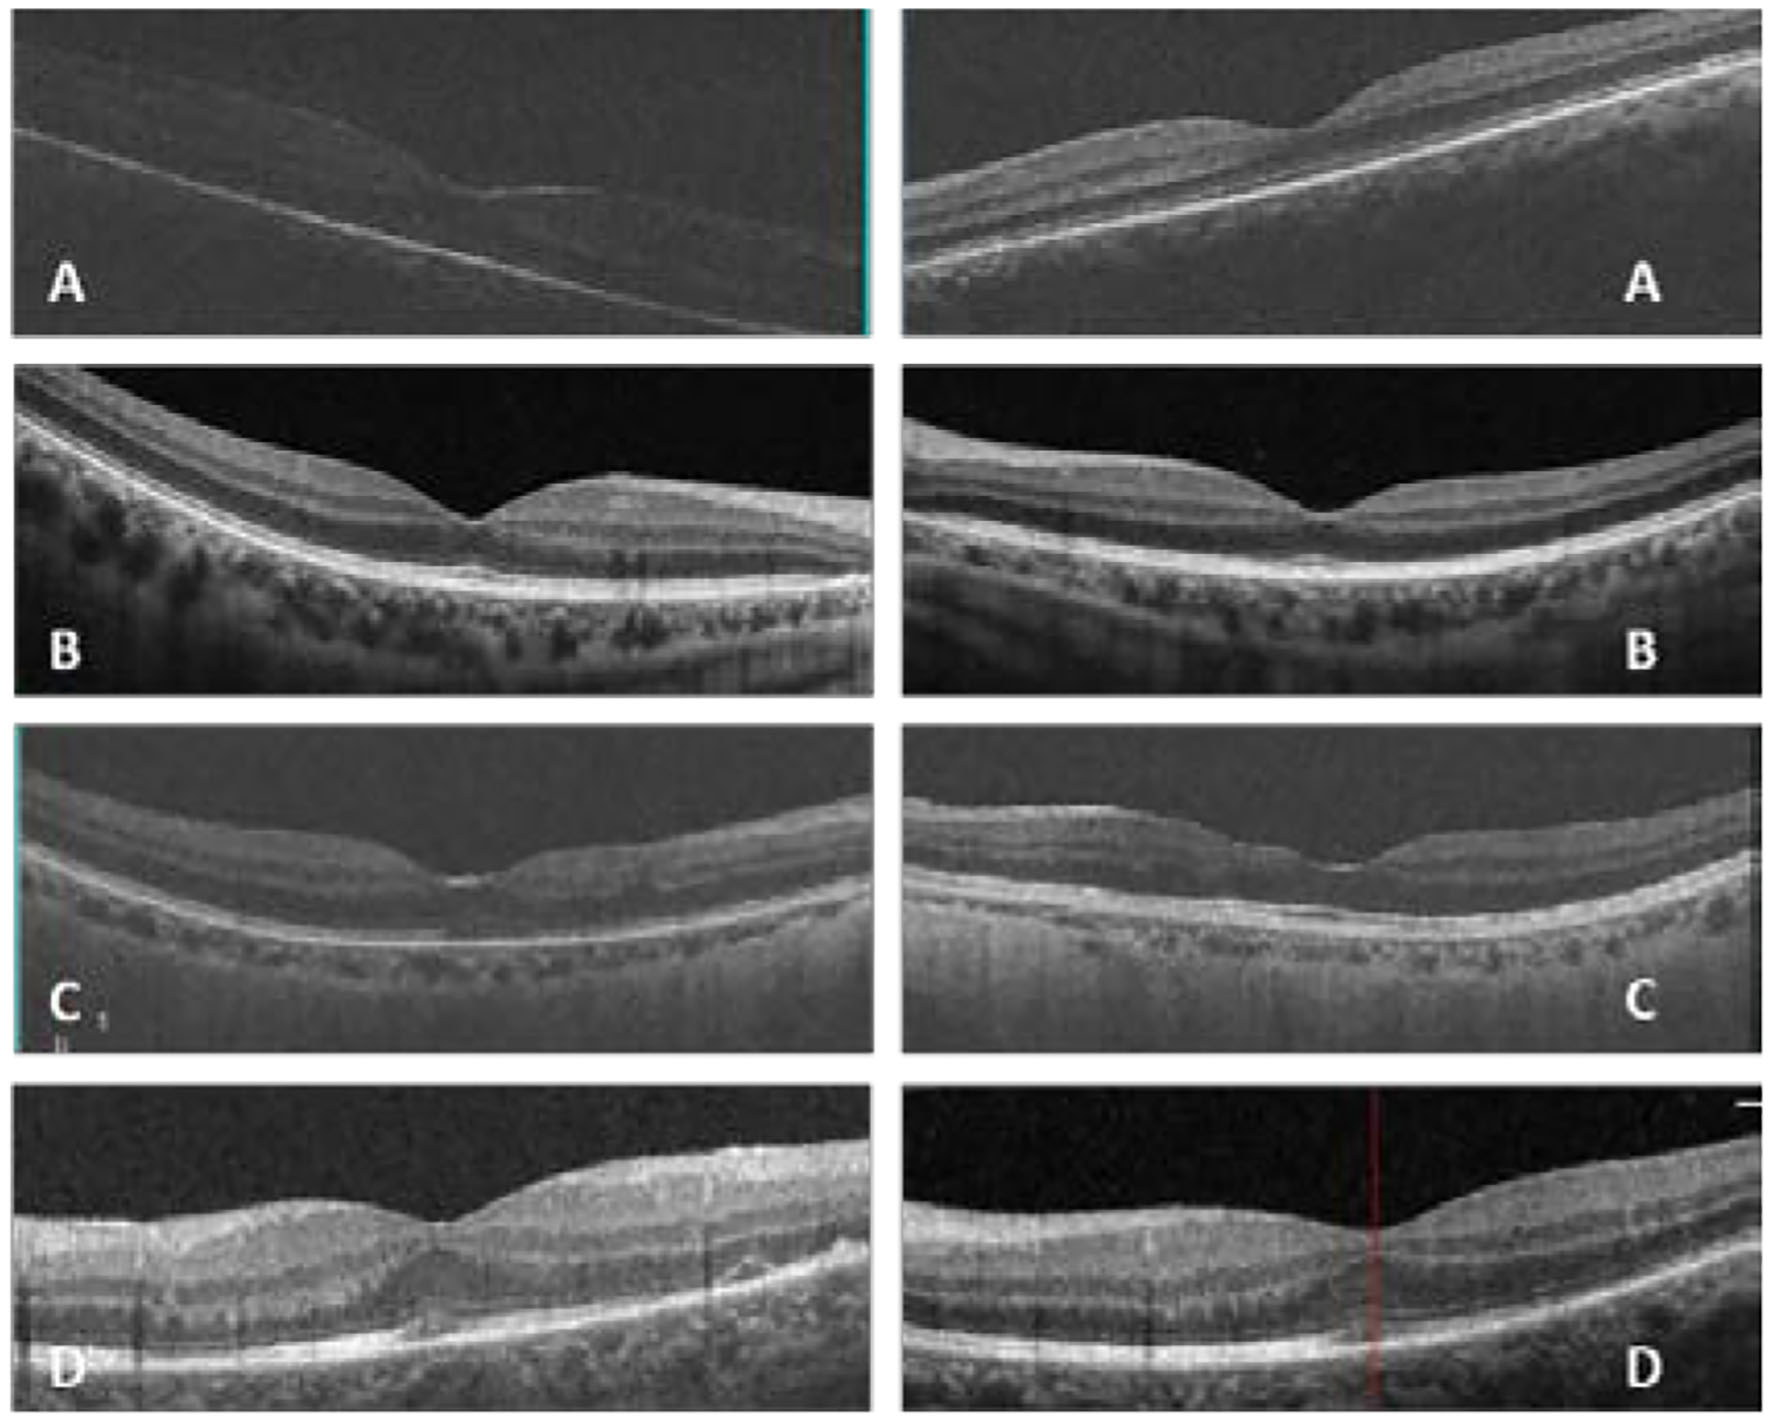

Figure 2

In patient one (A), optic coherent tomography (OCT) showed an epiretinal membrane in macular in the right eye; in patient two (B), OCT was normal in macular in both eyes; in patient three (C), OCT showed a slight epiretinal membrane and inner retina disorder in macular in both eyes; in patient four (D), OCT showed a slight epiretinal membrane and a minor retinal neurosensory layer detachment in the left eye (Left: the right eye, right: the left eye, (D) shows only the left eye for the atrophy of the right eye).

In our study, all four patients were progressed with active CMVR lesions with immune recovery within 8 weeks of HAART initiation. Characteristics of the four CMV-IRR patients with HIV positive are summarized in Table 1. Among the four patients, the mean CD4 T cells were 14.5/μl at the HIV diagnosis and 183.25/μl at the CMV-IRR diagnosis. All four patients had an obvious increase of CD4 T cells over 100/μl from a very low baseline (<40/μl). They came to our ophthalmology department and presented with progressed blurred vision without any ophthalmological examination or treatment. The slit lamp showed vitritis and retinitis without anterior segment abnormalities. The vitreous activity was evaluated according to the grading system (1+ to 4+) proposed by Nussenblatt et al. (7). Fundus examination including mydriasis fundus examinations, ultrasound B scans, and OCT scans was performed in the four patients. The fundus showed typical necrotizing retinitis, intraretinal hemorrhages, and vasculitis (Figure 1, patient four). Three patients had retina lesions in zones 2 and 3, while the other patient had retina involvement in zones 1–3. OCT showed normal in one patient and a slight epiretinal membrane in macular in two patients. The other patient had a minor retinal neurosensory layer detachment in the macular (Figures 2A–D). Ultrasound B scans demonstrated obvious vitritis in all four patients (Figures 3A–D). PPV was done and vitreous samples were aspirated for next-generation sequencing. The results demonstrated a high copy of the CMV sequence ranging from 60,527 to 445,532.